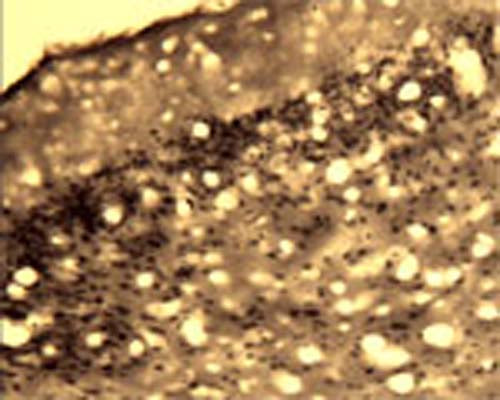

Anti-Activity-regulated gene 3.1 protein homolog (Arg3.1) Antibody

Our Anti-Activity-regulated gene 3.1 protein homolog (Arg3.1) rabbit polyclonal primary antibody detects human, mouse, and rat Activity-regulated gene 3.1 protein homolog (Arg3.1), and is IgG. It is validated for use in IHC-Frozen.